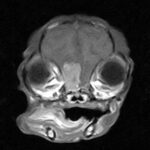

頻繁に嘔吐・下痢をするワンちゃんの精密検査依頼で内視鏡検査のご紹介がありました。内視鏡検査で上部・下部消化管を検査し、粘膜を採取し病理組織検査に出しました。結果は「胃:らせん菌感染を伴う慢性胃炎(中程度)/結腸:慢性腸炎(軽度)」とのことでした。その後かかりつけの先生のところ […]